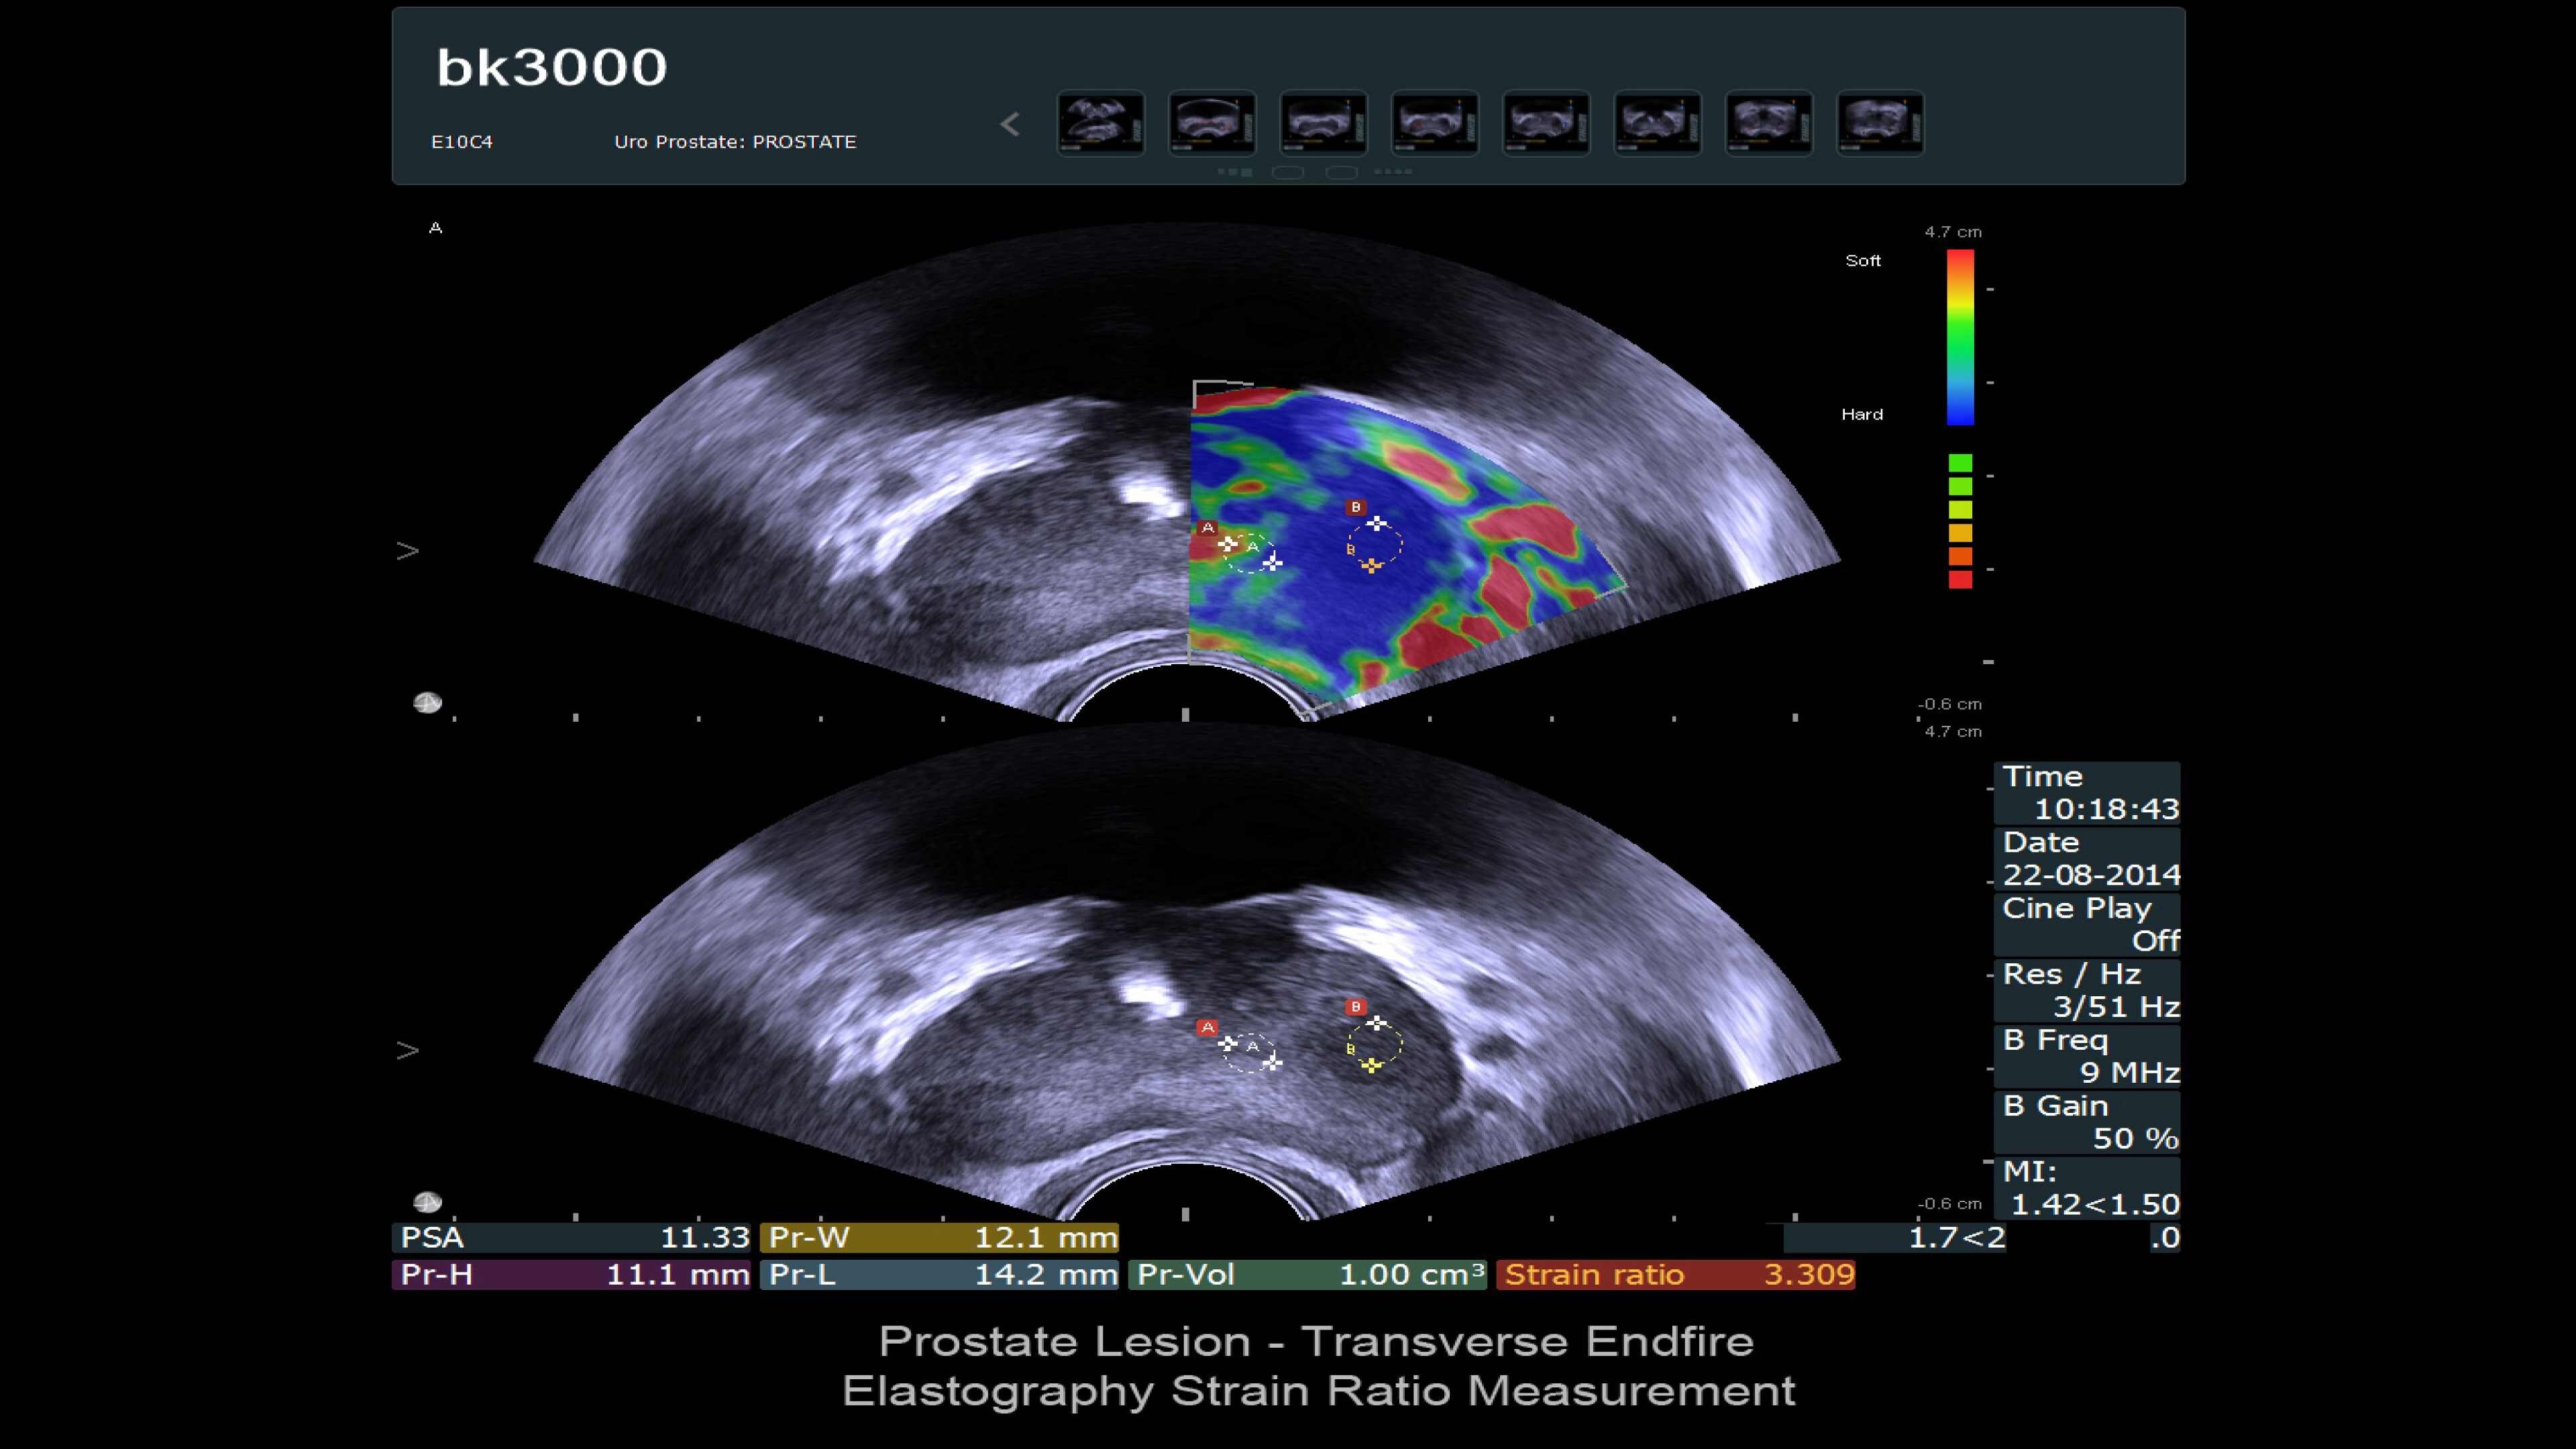

The bk3000 ultrasound machine offers ultra high-resolution imaging for urology, including exceptional prostate, kidney, bladder, and testes imaging. It features real-time, high-definition prostate images, elastography for targeted biopsies, and a unique Triplane transducer for simultaneous biplane and endfire imaging. The system enhances lesion targeting with fusion-guided biopsies, combining MRI and ultrasound for precision prostate biopsies. Advanced imaging features and dedicated transducers improve visualization and treatment confidence during prostate interventions.